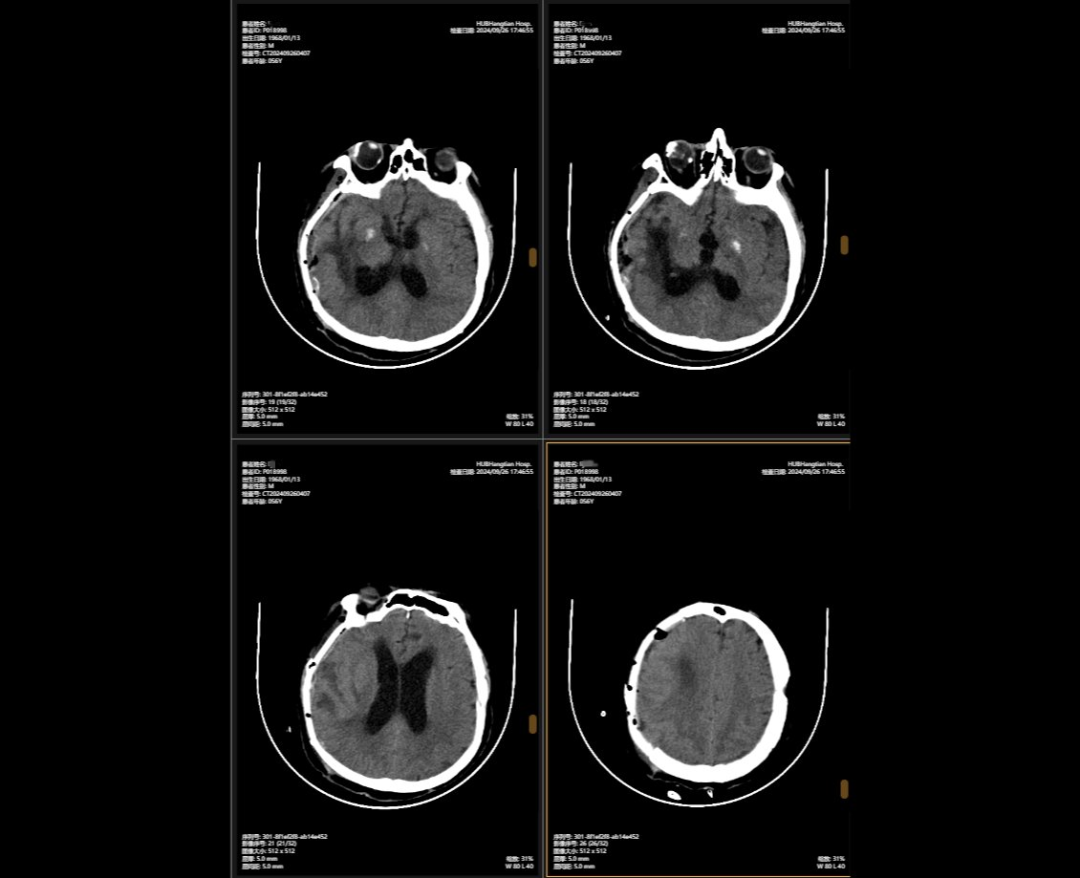

2024年5月,56岁的李某(化名)不幸遭遇严重车祸。他当场陷入昏迷,情况危急。被送往湖北航天医院后,检查结果让大家担心不已。他头部被重击,不仅多处出血,脑组织淤青,连呼吸和心跳的“指挥中枢”脑干也受损。此外,颅骨、颈椎、肋骨多处骨折,情况极为危急。

李某头上的多处伤口就像一颗“炸弹”,随时都有生命危险。面对如此复杂的颅内损伤,航空医学神经外科团队接到诊断后,神经外科主任陈义勇迅速做出了决定。他迅速发起多学科会诊,同时精心准备手术。多学科团队紧急召开会议,讨论了d 制定了详细的手术计划。手术方案确定后,神外团队争分夺秒地对李先生进行了多处颅内血肿清除+颅内减压+右侧开颅+颅骨切除+左侧硬膜外血肿清除+矢状窦破裂止血。手术中,医生进行精准手术,成功止血,最大限度地保护了正常脑组织,给李先生带来了生存的希望。

颅骨缺损修复手术前后对比